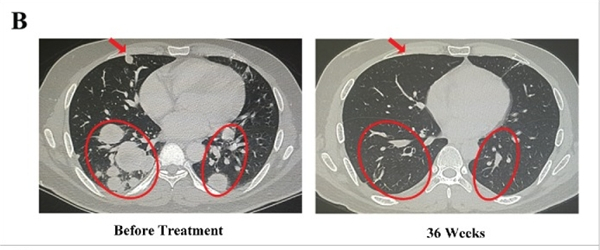

在RCC(肾细胞癌)患者中,客观RR和DCR分别为25%和75%,包括1个CR、1个PR和4个稳定疾病。达到CR的患者是一名34岁的男性(图B),在手术和阿昔替尼治疗后出现广泛的双侧肺转移和持续进展的疾病。在开始治疗后36周,他的转移性疾病完全消退。该患者继续接受维持治疗并经历CR。另一名部分反应者是一名 31 岁女性(图C),她在姑息性手术后出现大量腹水和多处腹膜后淋巴结转移。在派姆单抗(PD1抑制剂)激活的自体DC-CIK细胞输注开始后的12周内,这些腹水几乎消失,淋巴结转移灶减少。然而,由于贫血、血清AST和ALT水平升高以及甲状腺功能减退,她要求在16个周期后停止治疗。有趣的是,该患者在最近的一次随访中继续经历PR(超过240天)。

实现CR(完全缓解)的肾癌患者